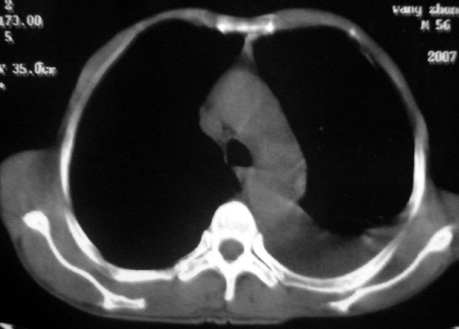

男,54岁,咳嗽,气喘半年,胸痛一月.

血性胸水

支持左肺下叶中心型肺癌(累及舌叶)伴阻塞性肺炎、膨胀不全、胸腔积液、心包少量积液。

考虑左肺下叶中央型肺癌伴阻塞性肺炎及肺不张,纵隔受累可能,胸膜转移。